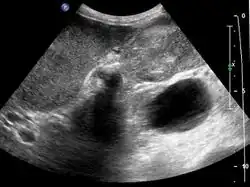

Early diagnosis is not generally possible. People at high risk, such as women or Native Americans with gallstones, are evaluated closely. Transabdominal ultrasound, CT scan, endoscopic ultrasound, MRI, and MR cholangio-pancreatography (MRCP) can be used for diagnosis. A large number of gallbladder cancers are found incidentally in patients being evaluated for cholelithiasis, or gallstone formation, which is far more common.[13] A biopsy is the only certain way to tell whether or not the tumorous growth is malignant.[14]

Gallbladder carcinoma on ultrasound